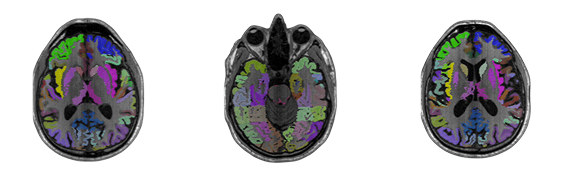

CLINICAL MRI + AI INSIGHTS Beyond a standard MRI – a deeper view of your brainYou receive a full medical MRI scan with a certified radiologist’s report. On top of that, our AI visualizes your brain in 3D and extracts metrics like Neuroplasticity Score, Cognitive Age, and Memory Index — giving you the context behind the diagnosis and showing how your brain evolves over time.Your insight grows with scienceMRI data stays securely with the user while analysis models keep improving.As new AI and neuroscience discoveries appear, past scans are reinterpreted with the latest understanding.This provides updated insight into focus, resilience, and cognitive balance, keeping each person in step with advancing brain science. PERSONALIZED PERFORMANCE PATHWAYS Recommendations shaped by your brain and your interestsInsights are personalized using your MRI data and the activities you care about — whether it’s focus at work, creativity, or athletic performance.The system translates your brain metrics into clear, science-based actions that help you train attention, balance stress, and build mental endurance for the goals that matter most.INTEGRATED HEALTH CONTEXT Connect your brain data with your daily signalsHelloMRI integrates with Apple Watch, WHOOP, and other wearables to combine your brain metrics with sleep, recovery, and stress data. Together, they form a continuous picture of how your mind and body interact — giving you a deeper context for focus, resilience, and long-term performance.How It Works

Receive your 3D brainDelivered within 72 hours with insights and optional NFT.Interactive visualization with personalized brain-age estimation and longevity metrics.